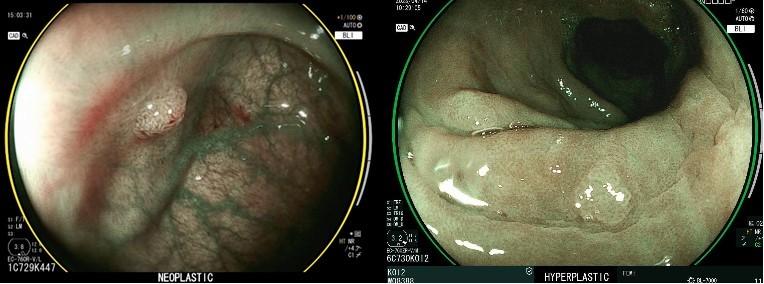

亞東醫院超音波內視鏡中心鍾承軒主任表示,「CAD EYE人工智慧內視鏡影像系統」能夠提升並輔助醫師在執行內視鏡檢查和治療時的準確性。檢查過程中,系統利用白光影像(圖一可見AI藍色框起部分在一般肉眼判斷可能忽略)和連動彩色影像模式進行偵測,當發現異常時,會以藍色框提醒醫師疑似的瘜肉或腫瘤,靈敏度可達94%至96%,優於過去經驗判讀。且在使用藍光影像模式(圖二)觀察時,AI功能即時診斷和鑑別瘜肉表面結構,將其分類為增生性瘜肉或腫瘤性瘜肉,增生性瘜肉日後轉變為惡性腫瘤的機率較低,腫瘤性瘜肉未來癌化的風險相對高,則建議切除。

圖說:藍光大腸內視鏡影像模式下,AI系統能夠即時進行診斷和鑑別,將檢測到的疑似瘜肉分類為增生性瘜肉或腫瘤性瘜肉。提供了醫師在治療上所需的內視鏡資訊。